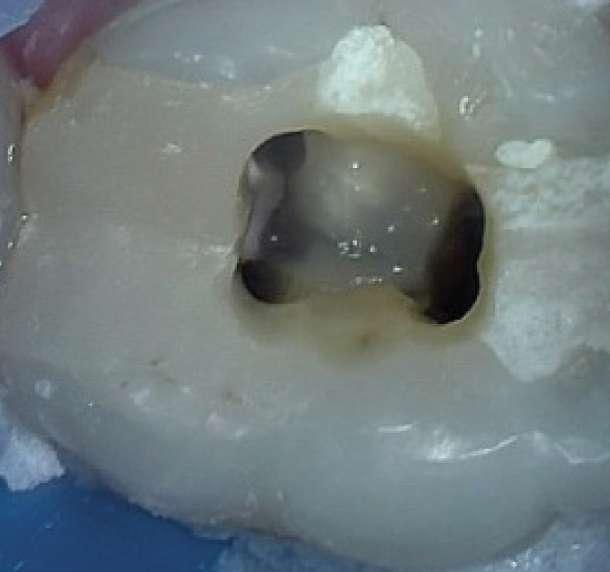

Die Revisionsbehandlung erfolgte in zwei Sitzungen. Nach Anlegen des Kofferdams wurde die provisorische Füllung entfernt und die Zugangskavität gereinigt. Im Anschluss erfolgte die intrakoronale Diagnostik (Abbildung 11). Es zeigte sich bakteriell besiedeltes Wurzelfüllmaterial im mesiobukkalen, distobukkalen und palatinalen Kanal. Das Orifizium des mesiobukkalen Kanals war in palatinaler Richtung erweitert. Die Entfernung eines mesialen Dentinüberhangs mit langschaftigen Rosenbohrern legte das weit nach palatinal verlagerte Orifizium des zweiten mesiobukkalen Kanals frei. Die Entfernung des Wurzelfüllmaterials erfolgte mithilfe von EdgeFile X7 der Größe 25.06, und 17.06 in Crown Down Technik um die Verschleppung von Keimen und bakteriell besiedeltem Wurzelfüllmaterial nach apikal zu reduzieren. Die Erschließung und initiale Aufbereitung des zweiten mesiobukkalen Kanals wurde mithilfe der EdgeFile X7 der Größe 17.04, 17.06 in alternierender Weise wie oben beschrieben durchgeführt. Nach elektrometrischer Bestimmung der Arbeitslänge aller Kanäle wurde die Präparation mit EdgeFile X7 auf voller Arbeitslänge fortgesetzt. Im ersten mesiobukkalen Kanal, distobukkal und palatinal wurde die Aufbereitung mit EdgeFile X7 der Größe 40.06 abgeschlossen, während der zweite mesiobukkal Kanal bis 30.06 aufbereitet wurde (Abbildung 13).

Abbildung 11: Nach Ausarbeiten der primären Zugangskavität; Darstellung des mb2 in der Nähe des palatinalen Kanals